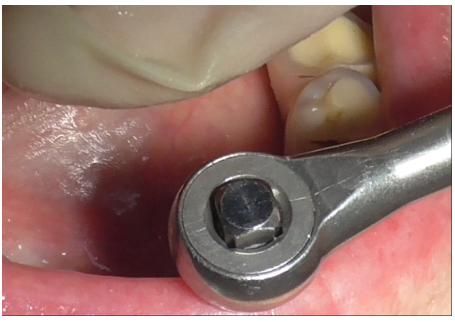

Removal of the prosthetic structure began by eliminating cement covering the prostethic abutment (Figures 3-5), followed by unscrewing the abutment (Figure 6) to facilitate the removal of the prosthesis.

Figure 6